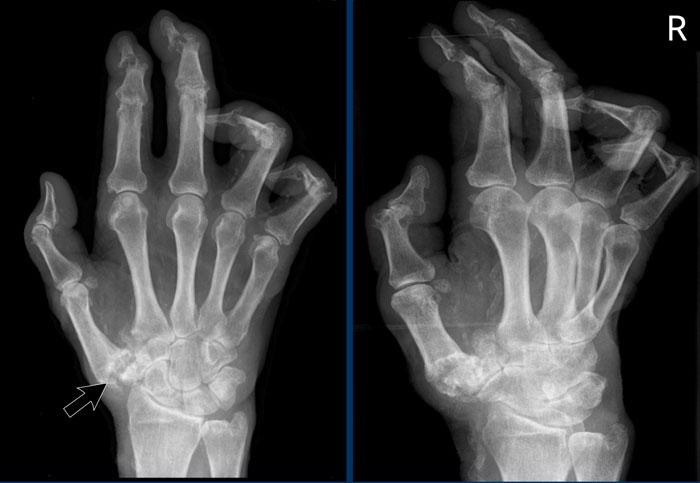

Hình ảnh bào mòn xương vùng rìa điển hình và hẹp khe khớp tại các khớp MCP 3-5.

Lưu ý hình ảnh hẹp khe khớp đồng đều tại các khớp MCP.

Các khớp liên đốt gần (PIP) chỉ biểu hiện hẹp khe khớp tối thiểu.

Đây là trường hợp viêm khớp dạng thấp giai đoạn cuối với các thay đổi bào mòn nặng nề và đứt dây chằng gây trật khớp tại các khớp MCP.

Phân ly xương thuyền – xương nguyệt (mũi tên trắng) là dấu hiệu thường gặp do tình trạng viêm lan tỏa khối xương cổ tay. Cả tình trạng phân ly lẫn viêm đều có thể gây hẹp khe khớp quay – cổ tay.

Lưu ý hình ảnh bào mòn xương đầu dưới xương trụ kèm theo sưng nề phần mềm xung quanh (mũi tên xanh).